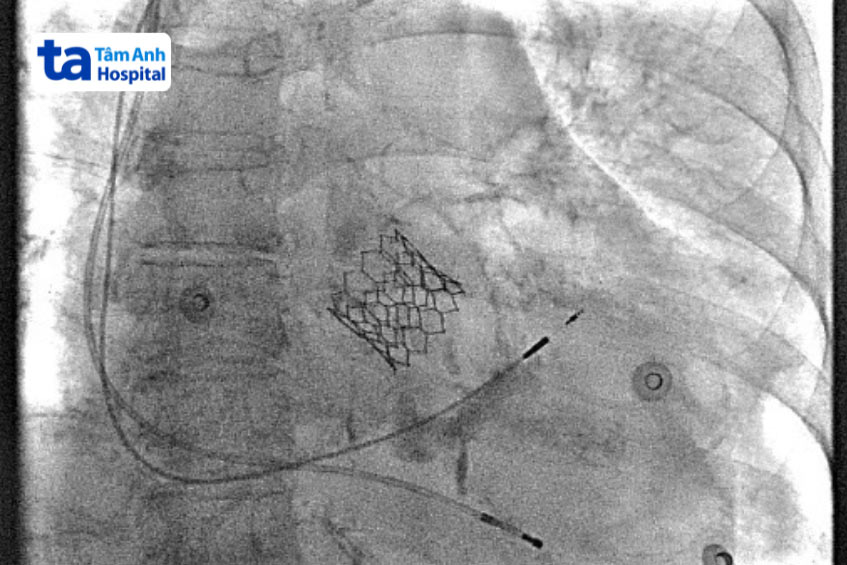

Thủ thuật này thay thế van từ bên trong bằng thiết bị ống thông. Bác sĩ sẽ thực hiện rạch một mạch máu lớn (thường ở cổ hoặc đùi trên) sau đó đưa ống thông vào. Ống thông sau khi được đưa vào, bác sĩ sẽ điều khiển thiết bị này lên tim của người bệnh, nơi họ đặt đầu ống phía trên van hiện tại.

Khi đến đúng vị trí, bác sĩ thực hiện mở rộng van mới, làm bẹp van cũ, hỏng bên dưới. Các van thay thế thường là sinh học và có thời gian sử dụng lên đến 15 năm.

Điều trị tình trạng này bằng TPVR có tỷ lệ thành công cao. Khoảng 94% đến 98% các thủ thuật TPVR đạt hiệu quả. Các biến chứng của TPVR cũng hiếm xảy ra, có khoảng 3% đến 6% các trường hợp xảy ra biến chứng phổ biến nhất là chèn ép động mạch vành hoặc viêm nội mạc do nhiễm trùng.